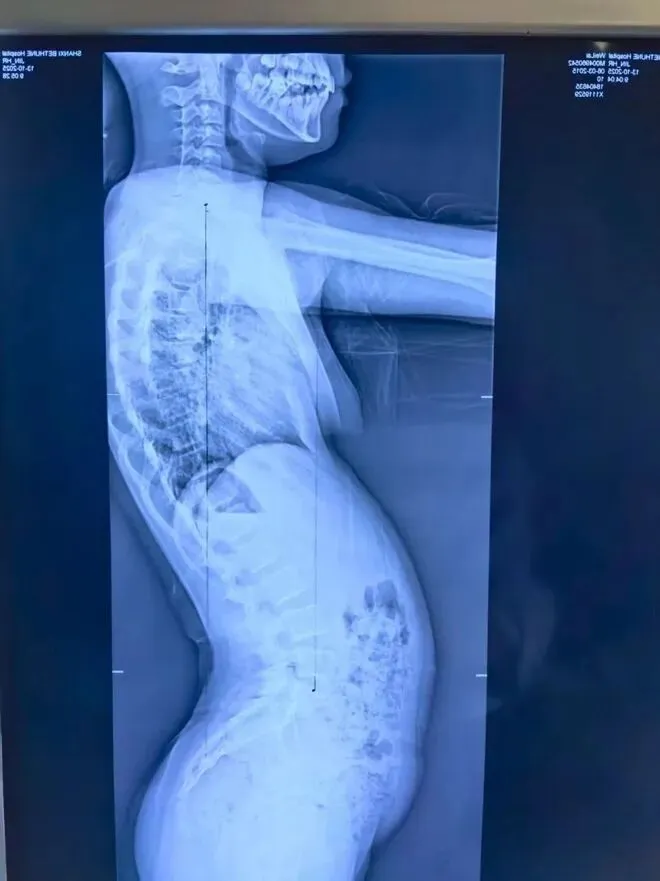

在门诊接诊的青少年中,“懒骨头体态” 最为普遍 —— 孩子总是含胸驼背、头向前探,腰椎看似放松却总也直不起来,整体姿势像一个软塌塌的 “问号”。家长们往往以为是孩子缺乏自律、不爱挺拔,但其实这是身体的 “被动选择”,本质是身体在 “挪出空间” 保护内脏,而非主动偷懒!

更值得警惕的是,这种 “懒骨头体态” 还会与脊柱侧弯相互影响:消化异常导致体态失衡,失衡的体态又会加重脊柱侧弯的进展,形成 “消化差→体态糟→侧弯重” 的恶性循环,不仅影响孩子的外形气质,还可能引发腰酸、腹胀、注意力不集中等问题。